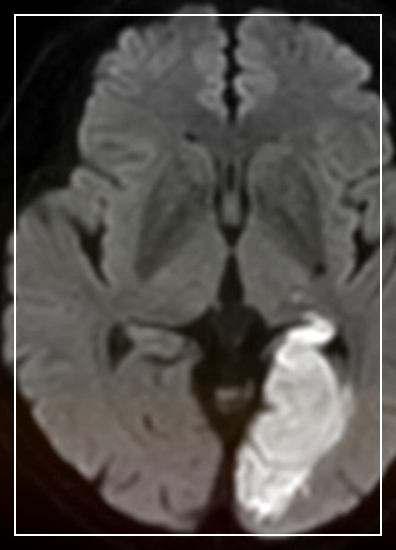

뇌 확산 MRI는 뇌 속 물 분자의 이동 방향과 속도를 측정하여 뇌의 미세 구조를 보다 정확하게 파악하는 영상 기법입니다. 일반적인 MRI가 뇌의 해부학적 구조를 보여주는 데 초점을 맞춘다면, 확산 MRI는 뇌의 기능적 연결성과 미세 구조 변화를 탐색하는 데 특화되어 있습니다.

뇌 질환 진단: 뇌종양, 뇌졸중, 뇌 백질 병변 등 다양한 뇌 질환의 진단과 병변의 특성 파악에 활용됩니다.

뇌 속 물 분자는 세포막, 신경섬유 등의 장애물에 의해 제한적으로 이동합니다. 확산 MRI는 이러한 물 분자의 이동 방향과 속도를 측정하여 뇌 조직의 미세 구조에 대한 정보를 얻습니다.

특히, 신경섬유 다발을 따라 물 분자가 더 빠르게 이동하는 현상을 이용하여 뇌의 연결망을 분석할 수 있습니다.